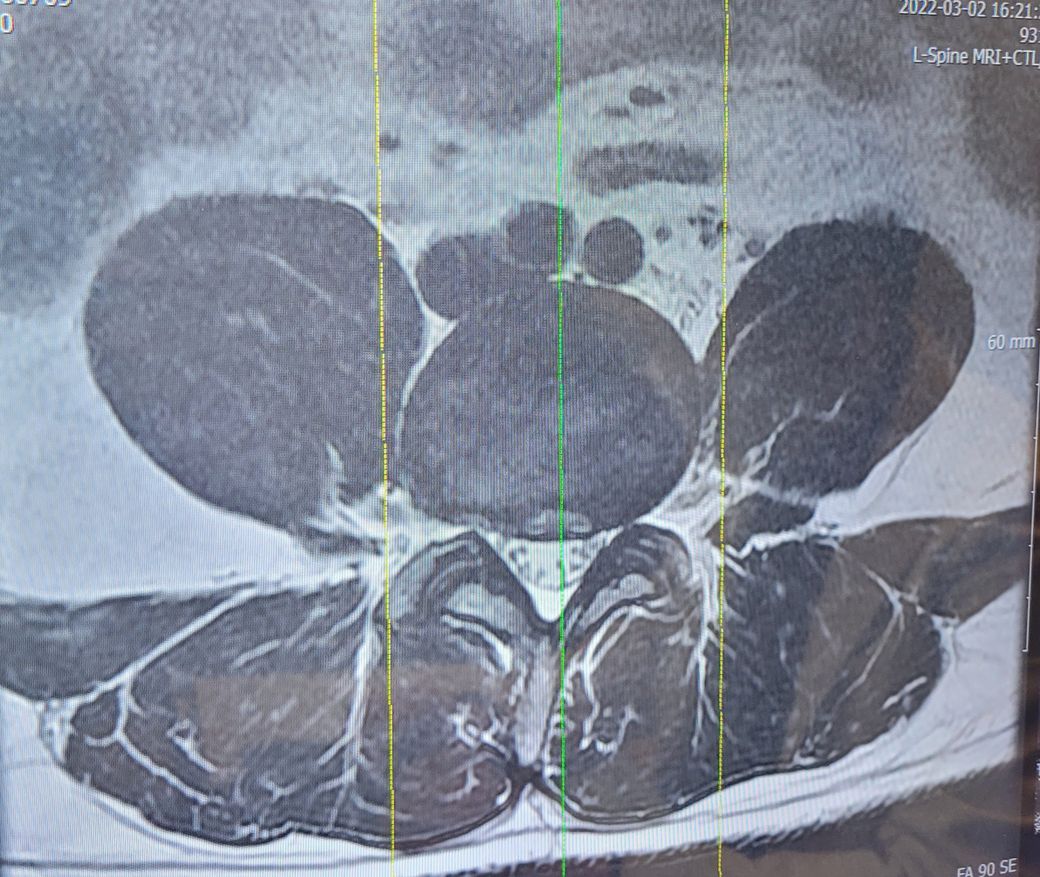

Sagital section 을 보았을 때에는 L2,3,4,5 가 모두 조금씩 눌려 있는데 이 중 L4-5, L5-S1 이 가장

많이 눌린 것으로 보입니다. 이 중 L5-S1 은 50% 이상 눌린 것으로 보이며 보통 수술결정은 추간판 수핵의

터진 상태에 따라 결정되며, 터진 추간판 수핵이 신경에 눌러 붙어 박리된 경우에는 반드시 수술이 필요하게

됩니다. 이때는 근력저하,하반신 마비와 함께 대소변에 장애, 발목에 힘이 들어가지 않아 밑으로 처지는 풋드랍

현상이 나타 나는데 이러한 증상이 나타날 때는 정확한 진단 후 수술적 치료가 필요합니다. 감사합니다.